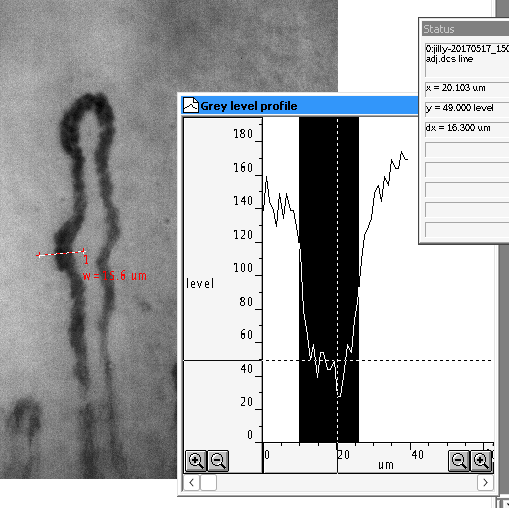

Single capillary line width measurement from active dimension line.¶

The width is measured from the greylevel profile. Better results can be achieved by increasing the line width to say 10 pixels. The greylevel is then averaged across the width of the measurement line.

Right click on the first node of the Dimension line to change its width. This width will also then become the new default line width.¶

Noisy greylevel profile with a dimension line width of only 1 pixel.¶